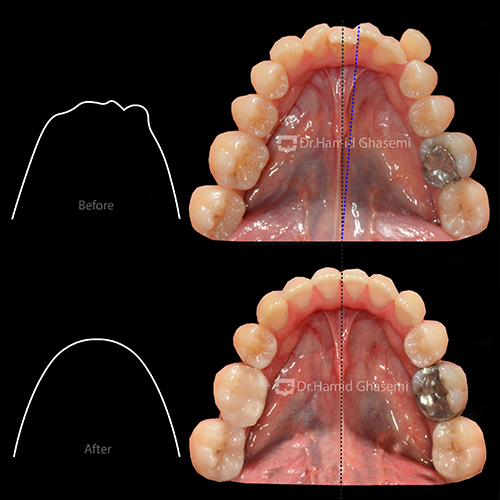

- تنگی نسبتاً شدید فک بالا

- انحراف شدید دندانی در فک پایین به میزان ۶ میلی متر به سمت راست

- انحراف دندانی فک بالا به میزان ۲ میلی متر به سمت چپ

درمان انحراف فک پایین که به علت شدت به هم ریختگی دندانها ناشی از تماسهای زودرس دندانی و در نتیجه شیفت فکی ایجاد شده بود در طول درمان به صورت خودکار بعد از اصلاح اکلوژن درمان شد.

تنگی فک بالا با استفاده از تکنیک MEAW در فک بالا درمان شد. لازم به ذکر است به دلیل استفاده از این تکنیک در کمترین زمان ممکن (۲ ماه) عریض شدن فک بالا بدون ایجاد Buccal Flaring دندانهای خلفی میسر شد.

- اصلاح انحراف میدلاین دندانی در فک بالا و پایین

- عریض شدن بیس فکی

- اصلاح زاویه فک پایین (Mandibular Angle)